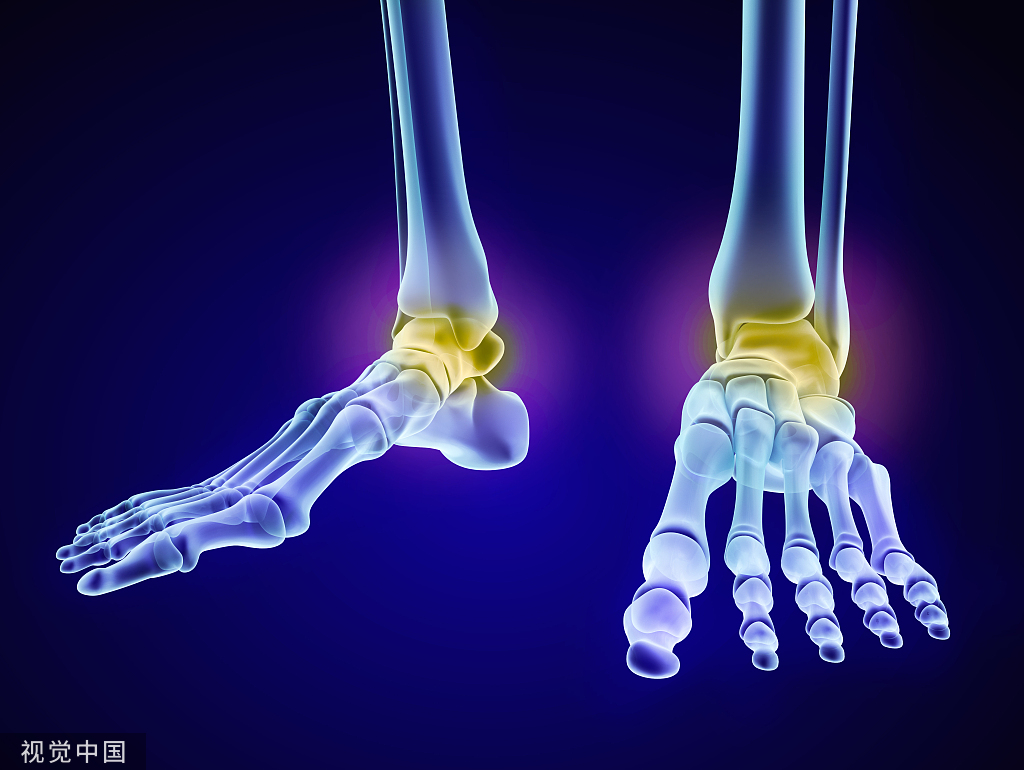

腓骨远端骨折的固定通常采用切开复位内固定(ORIF)。我们根据外侧植入物的特点,采用微创手术技术(MIS),可减轻伤口并发症。最近,Chiang等人发表了一项比较队列研究,证明MIS入路治疗腓骨远端骨折是可行的。

示例为44岁女性,糖尿病控制不良,扭伤导致踝关节双踝骨折,需手术固定。

1、患者取仰卧位,同侧髋下垫一个小垫子,轻微内旋肢体。触诊骨折部位,并在透视后在皮肤上标记出确切的位置。为了准确地切口在骨折部位上方,需要对踝关节进行侧位片检查。

2、在远端3-4厘米的切口上斜置,确定骨折部位。

3、注意避开腓浅神经。将骨折部位的软组织、骨膜或血肿清理干净使用尖头复位钳解剖复位骨折。

4、然后将钢板插入切口,按顺序向近端推入,使钢板远端进入切口,然后向远端推入。一旦在透视镜下确定了正确的位置,我们通常通过切口放置一颗皮质螺钉,以便将钢板固定在腓骨上。然后可以通过小切口置入2颗螺钉。

术后X线片: